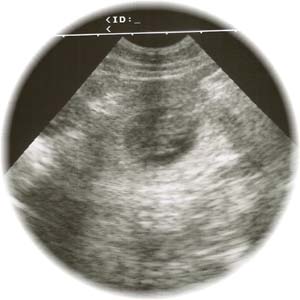

... und hier gibt es auch schon einmal das erste Schwarz-Weiß-Foto von einem unserer G-chen ... |